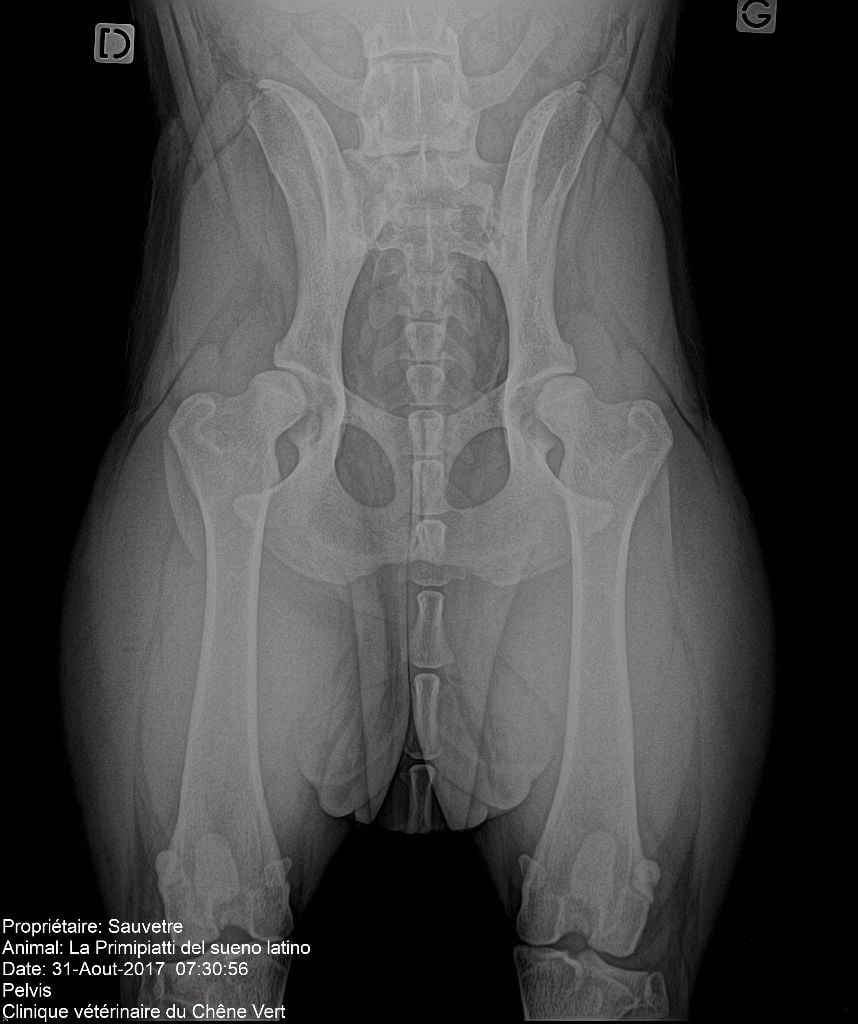

La primipiatti del Sueno Latino

Dogo Argentino

A.D.N. : identifiée + lien de parenté BAER TEST (surdité) : +/+ Dysplasie coxo-fémorale : C/B (par lecture officielle du club de race AFSDA) Dysplasie des coudes : 0/0 (par lecture officielle du club de race AFSDA) |